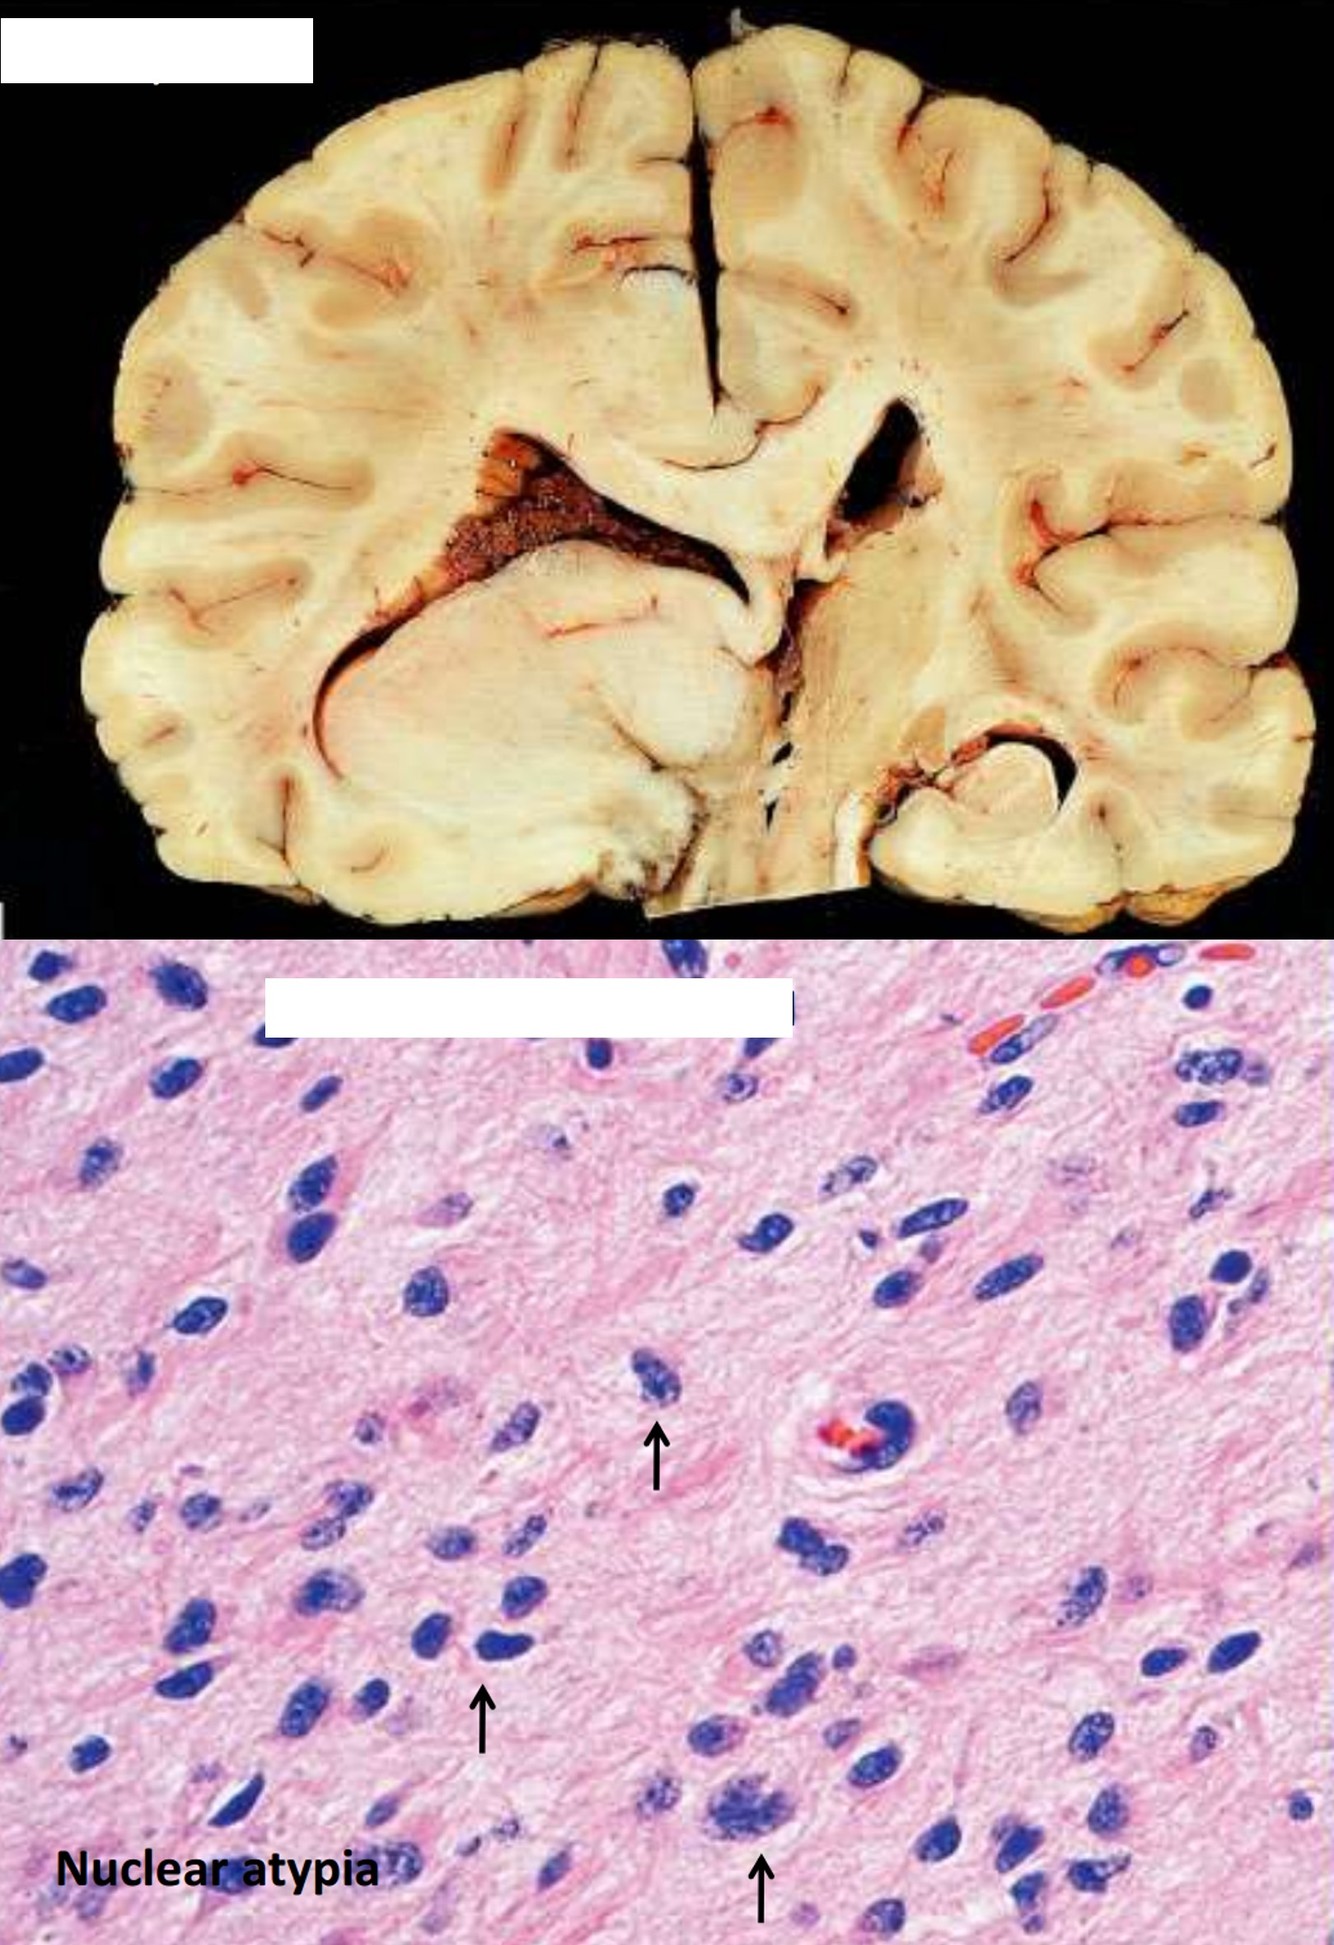

- Diffuse astrocytoma

Infiltrating Astrocytoma

Infiltrating Astrocytoma

- 80% of primary adult tumors

- WHO Grade II: diffuse astrocytoma

- Diffuse astrocytoma: 35 y/o